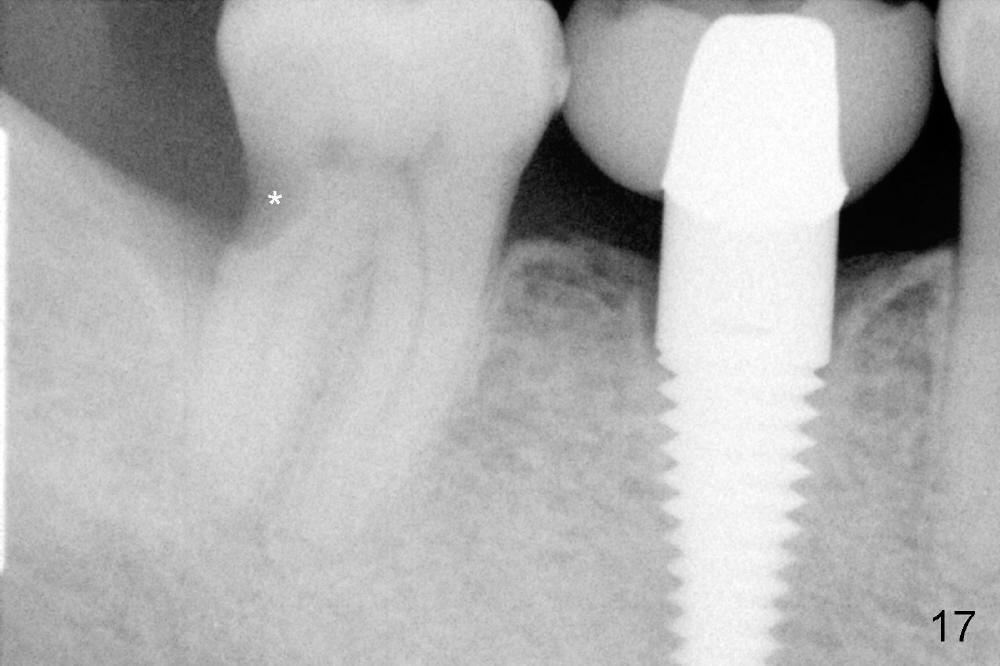

While the bone continues growing around the implant 1.5 years postop (Fig.17, as compared to Fig.12), the tooth #31 loses composite distally (*). A Zirconia onlay is cemented 1 year 10 months post implantation (Fig.18 arrowheads); the posterior interdigitation remains normal (Fig.19).